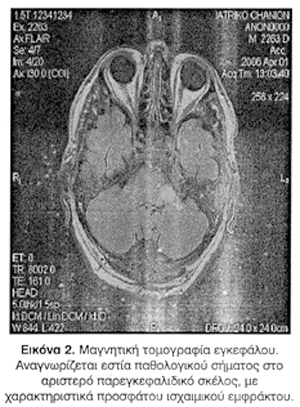

Η παρούσα νόσος ξεκίνησε με καρηβαρία επί 3-4 ώρες, και εν συνεχεία εμφανίστηκε ίλιγγος, οξεία πτώση ακοής και εμβοές αριστερού ωτός. Από την κλινική εξέταση αξιοσημείωτος ήταν ο νυσταγμός δευτέρου βαθμού προς τα δεξιά και η θετική δοκιμασία Romberg. Κατά τον ακοολογικό έλεγχο δεν εκλύθηκε το αντανακλαστικό του μυός του αναβολέα ομόπλευρα (ipsilateral) αλλά εκλύθηκε ετερόπλευρα (contralateral) με ένταση ηχητικού ερεθίσματος 100dB, ενώ στο τονικό ακοόγραμμα, φάνηκε η σοβαρού βαθμού νευροαισθητήρια βαρηκοΐα αριστερά (Εικ. 1). Με αρνητική τη νευρολογική εξέταση για βλάβη του κεντρικού νευρικού συστήματος, ο ασθενής νοσηλεύτηκε στην ΩΡΛ Κλινική με τη διάγνωση της πιθανής νόσου Meniere και τέθηκε σε αγωγή με πιρακετάμη και διμενυδρινάτη. Κατά τη διάρκεια του πρώτου 24ώρου εμφανίστηκε επιδείνωση της κλινικής εικόνας του ασθενή. Στη δεύτερη νευρολογική εξέταση, εμφάνιζε αυτόματο νυσταγμό που άλλαζε φορά ανάλογα με τη στροφή του βλέμματος, και σοβαρού βαθμού αστάθεια (ο ασθενής δεν ορθοστατούσε) ενώ παρέμενε η βαρηκοΐα αριστερά. Ο ασθενής υποβλήθηκε σε υπολογιστική τομογραφία εγκεφάλου, 35 ώρες μετά την έναρξη των συμπτωμάτων του, η οποία ήταν αρνητική για πρόσφατη ισχαιμική εστία σε στέλεχος ή παρεγκεφαλίδα. Στην αγωγή του προστέθηκε αντιαιμοπεταλιακή αγωγή. Σε νευρολογική επανεξέταση 8 ώρες αργότερα, και ενώ ο ασθενής ανέφερε υποκειμενική βελτίωση, εμφάνιζε εστιακή νευρολογική σημειολογία ως παρέκκλιση στην καθιστή και όρθια στάση προς αριστερά, δυσδιαδοχοκινησία και δυσμετρία αριστερών άκρων. Ο ασθενής μεταφέρθηκε στη Νευρολογική Κλινική και υποβλήθηκε σε μαγνητική τομογραφία εγκεφάλου, που ανέδειξε διάσπαρτες μικρές εστίες παθολογικού σήματος στον ακτινωτό στέφανο, ημιωοειδή κέντρα και εν τω βάθει υποεπενδυματική και λευκή ουσία που παριστούν ισχαιμικά έμφρακτα (lacunes) διαφόρου χρόνου εμφάνισης σε έδαφος ισχαιμικής λευκοεγκεφαλοπάθειας. Επίσης αναγνωρίστηκε μεγαλύτερη εστία παθολογικού σήματος στο αριστερό παρεγκεφαλιδικό σκέλος, με χαρακτηριστικά προσφάτου ισχαιμικού εμφράκτου (Εικ. 2).